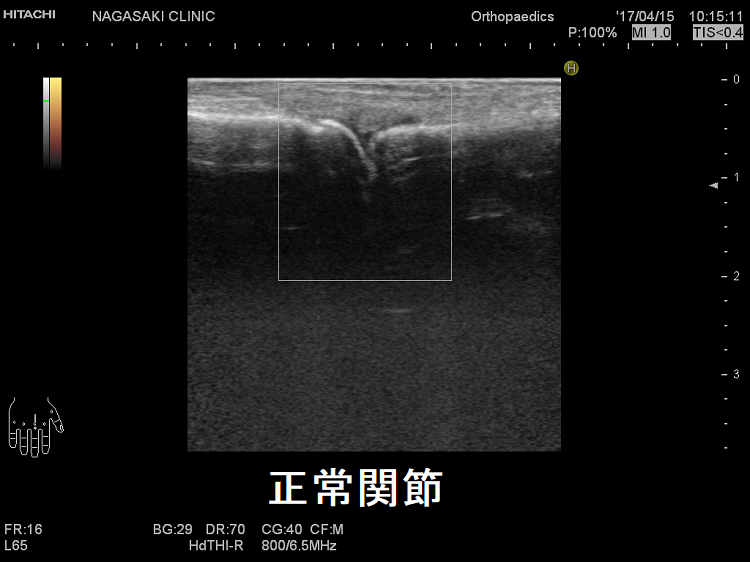

抗CCP抗体陰性なら、増殖した関節滑膜を関節超音波(エコー)検査で見つけます。これには長崎甲状腺クリニック(大阪)と同じレベルの高性能超音波(エコー)診断装置が必要です。

関節エコー検査